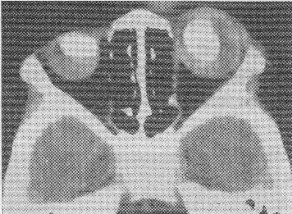

男孩,2歲,雙眼疼痛1年,右側(cè)眼球突出。CT平掃如圖:

正確答案:3.A;4.D 解題思路:視網(wǎng)膜母細(xì)胞瘤是兒童眼球內(nèi)最常見的惡性腫瘤,多見于3歲以下的幼兒,多數(shù)為單眼發(fā)病,約1/4的病人雙眼發(fā)病,CT表現(xiàn)為眼球內(nèi)實(shí)性腫塊,若伴有斑塊或斑點(diǎn)狀鈣化則較具特征。腫瘤較大致眼球增大、突出。視網(wǎng)膜母細(xì)胞瘤為起源于視網(wǎng)膜的胚胎性惡性腫瘤。